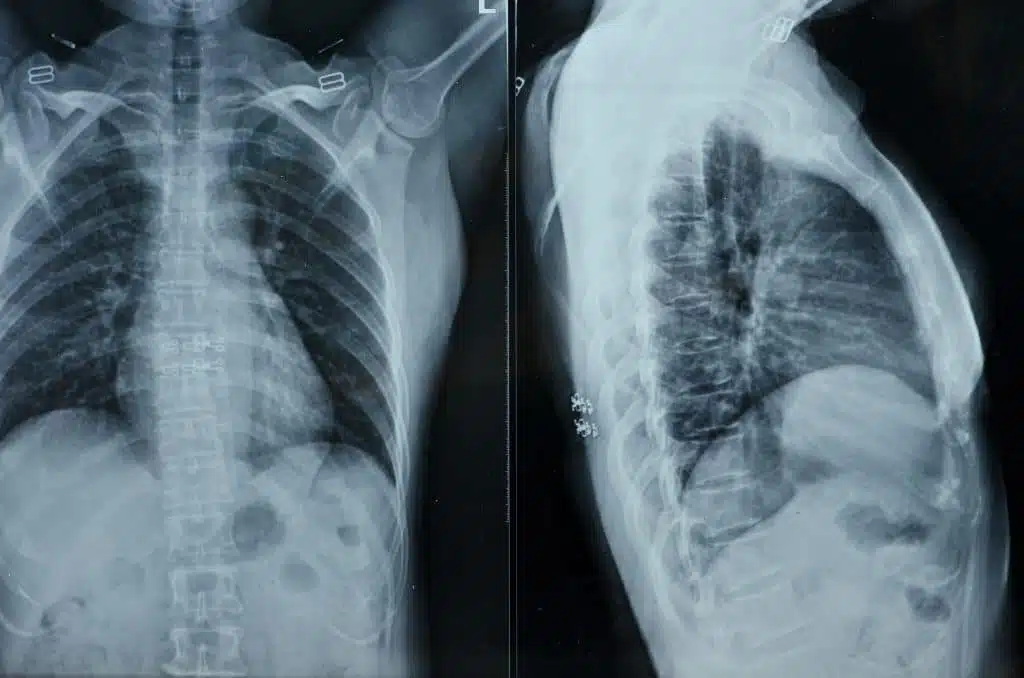

Traditional radiography has been used to capture images in medical fields ranging from dentistry to orthopedics for over a century. Traditional radiography makes use of directed X-rays (short wavelike forms of electromagnetic energy carried by particles called photons) to superimpose images of the human body onto sheets of specialized film. Though traditional radiography has been historically quite effective in capturing medical images, it is not without its drawbacks. The sensitivity of both the film and the X-ray machine itself require great care in both the image-capturing and development stages. The slightest amount of human error can often result in a ruined image. Traditional X-rays also emit a sizeable amount of radiation, which can be a concern for certain patient groups.

Digital radiography uses specialized electronic sensors to receive rays from an X-ray machine. Made from state-of-the-art hardware, the electronic sensors used in digital radiography can be produce images of considerably higher quality than those produced by traditional X-rays. Digital X-ray sensors are also considerably more sensitive than traditional film, which means that they require significantly less radiation per image.